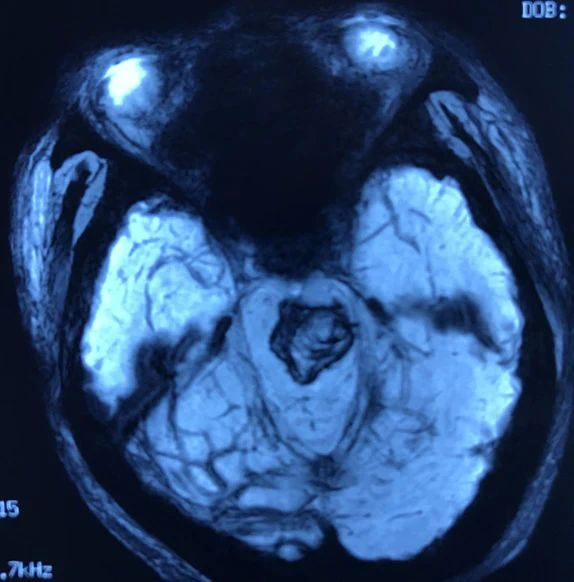

病人多发脑海绵状血管畸形,本次出血部位位于桥脑。第一次出血,术前偏瘫,转入我病房时为出血一月左右,采取颞下岩前入路切除脑干病变,术后病人肢体肌力较术前有提高,目前尚未出院。

本次手术资料: